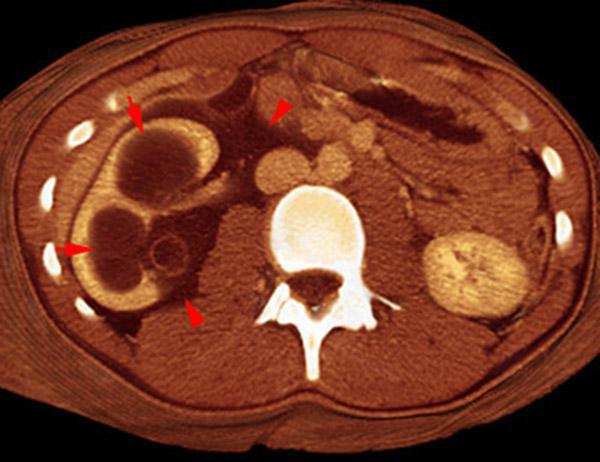

Hematoma subcapsular y perirrenal